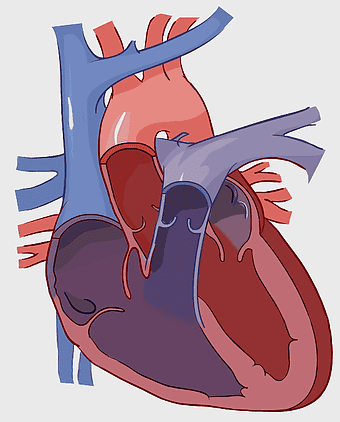

- heart and lung anatomy

Heart Anatomy Diagram, human heart drawing, realistic heart illustration, cardiovascular system, medical illustration, organ structure, human anatomy study -

human heart diagram, cardiovascular system anatomy, blood vessel chart, free body diagram, circulatory system illustration, medical organ visualization, human anatomy study -

human heart anatomy, cardiac muscle illustration, circulatory system model, heart health visual, cardiovascular organ diagram, medical heart image, visceral structure depiction -

human heart anatomy, red heart illustration, heart organ diagram, heart muscles and valves, cardiovascular system diagram, human body organ chart, anatomical heart structure -

human heart anatomy, superior vena cava illustration, systemic circulation diagram, heart rate visual, cardiovascular system study, medical organ depiction, human body organ reference -

heart anatomy diagram, human heart ventricle, human body physiology, heart beat animation, cardiovascular system, medical illustration, organ structure analysis -

human heart illustration, cardiac anatomy diagram, heart blood vessels, medical organ visuals, cardiovascular system chart, human anatomy study, circulatory system illustration -

heart anatomy illustration, cardiovascular system diagram, circulatory system medical, vascular system sonography, human body blood flow, arterial network visualization, heart function analysis -

heart anatomy diagram, circulatory system illustration, superior vena cava label, inferior vena cava structure, cardiovascular system chart, human heart ventricles, medical education graphics -